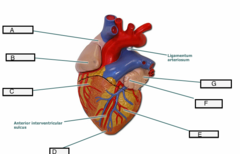

Anterior interventricular sulcus

Posterior interventricular sulcus

Circumflex branch (of the left coronary artery)

interventricular branch of the left coronary artery. = left anterior descending artery (LADA))

B & F

Left/right coronary artery